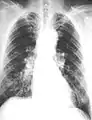

Extensive fibrosis of pleura and lung parenchyma

61-year-old working industrially with asbestos for decades

The abnormal chest x-ray and its interpretation remain the most important factors in establishing the presence of pulmonary fibrosis.[11] The findings usually appear as small, irregular parenchymal opacities, primarily in the lung bases. Using the ILO Classification system, "s", "t", and/or "u" opacities predominate. CT or high-resolution CT (HRCT) are more sensitive than plain radiography at detecting pulmonary fibrosis (as well as any underlying pleural changes). More than 50% of people affected with asbestosis develop plaques in the parietal pleura, the space between the chest wall and lungs. Once apparent, the radiographic findings in asbestosis may slowly progress or remain static, even in the absence of further asbestos exposure.[25] Rapid progression suggests an alternative diagnosis.